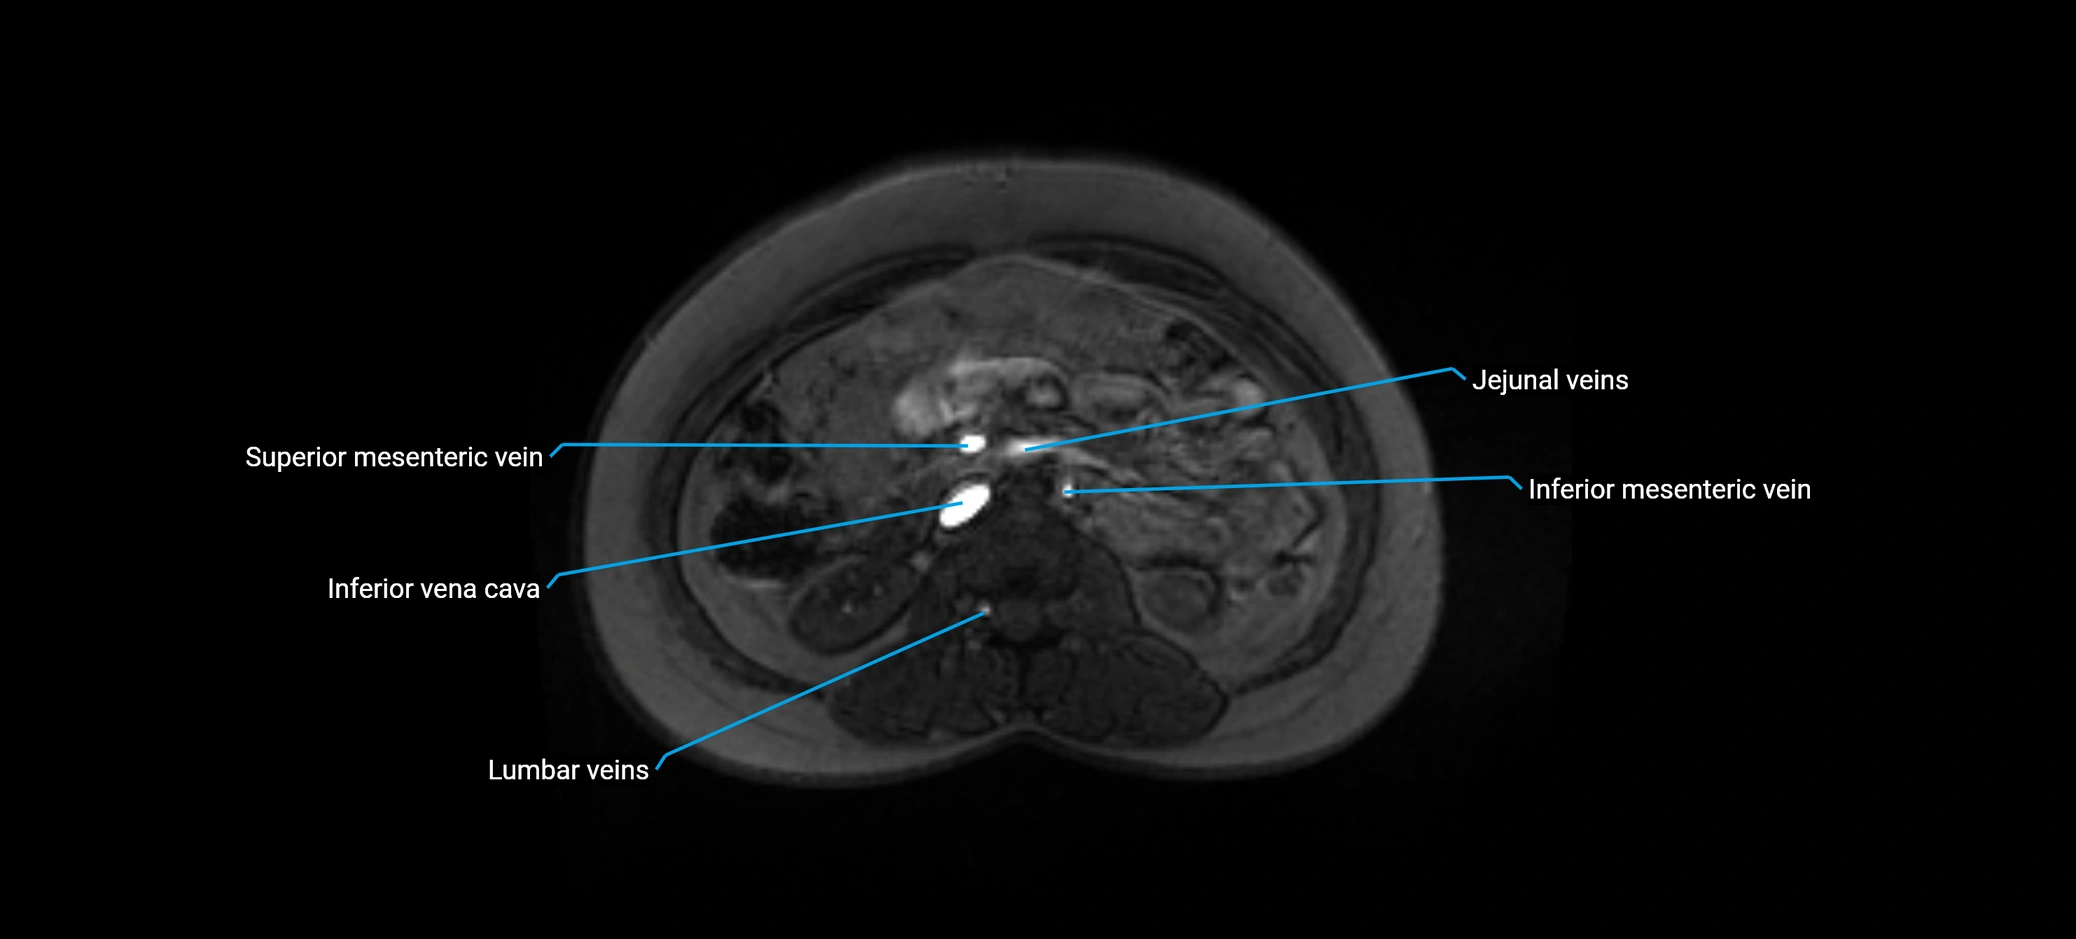

The anterior right branch of the portal vein is a major intrahepatic division of the right portal vein. After the main portal vein bifurcates into right and left branches, the right portal vein divides into anterior and posterior segmental branches.

The anterior right branch supplies the anterolateral liver segments (Segment V) and anteromedial liver segments (Segment VIII) within the right hepatic lobe. It operates as a key vascular route delivering nutrient-rich portal venous blood to the central and superior right liver.

This segmental vasculature is of major importance in hepatic surgery, embolization, segmental resection, transplantation, and imaging-based liver segmentation.